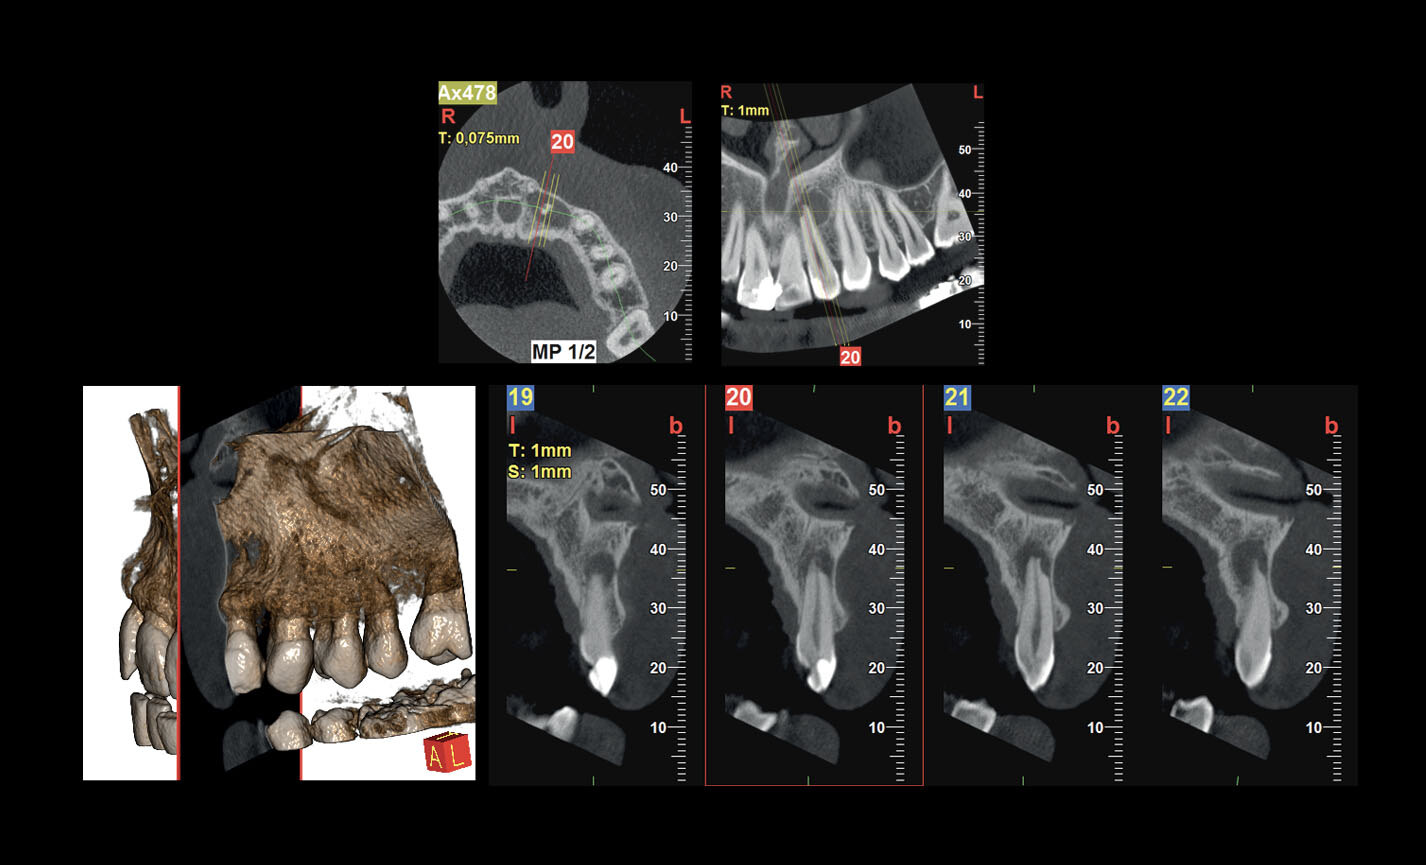

Des FOV de 10 cm de diamètre sont nécessaires pour l’étude des troisièmes molaires incluses car, chez un adulte de taille moyenne, la distance entre les troisièmes molaires de droite et de gauche, en incluant leurs racines respectives, le processus alvéolaire et l’os avoisinant, est d’au moins 9 cm. Les champs de vision réduits sont utiles en cas d’analyse de dents incluses ou surnuméraires, pour limiter la dose à la seule région d’intérêt. En effet, pour une planification correcte du traitement, il est fondamental de déterminer la position réelle (vestibulaire ou palatine), possible uniquement avec une analyse 3D, même à très faible dose avec un protocole QuickScan. Le champ de vision complet 13 x 16 cm permet une évaluation minutieuse des voies aériennes supérieures, souvent utile pour compléter une investigation en vue d’un traitement orthodontique qui tienne compte des problématiques oto-rhino-laryngologiques.

Planification implantaire avancée

Définissez la position de l’implant directement sur le modèle 3D, combinez-le avec les données STL provenant de scanners intra-oraux, et déterminez le projet prothétique définitif. Avec les instruments de planification implantaire avancée, vous pourrez opérer en toute sécurité, grâce aux informations précises sur la quantité d’os et la distance par rapport aux structures anatomiques avoisinantes, comme le canal mandibulaire, en définissant une distance minimale de sécurité.